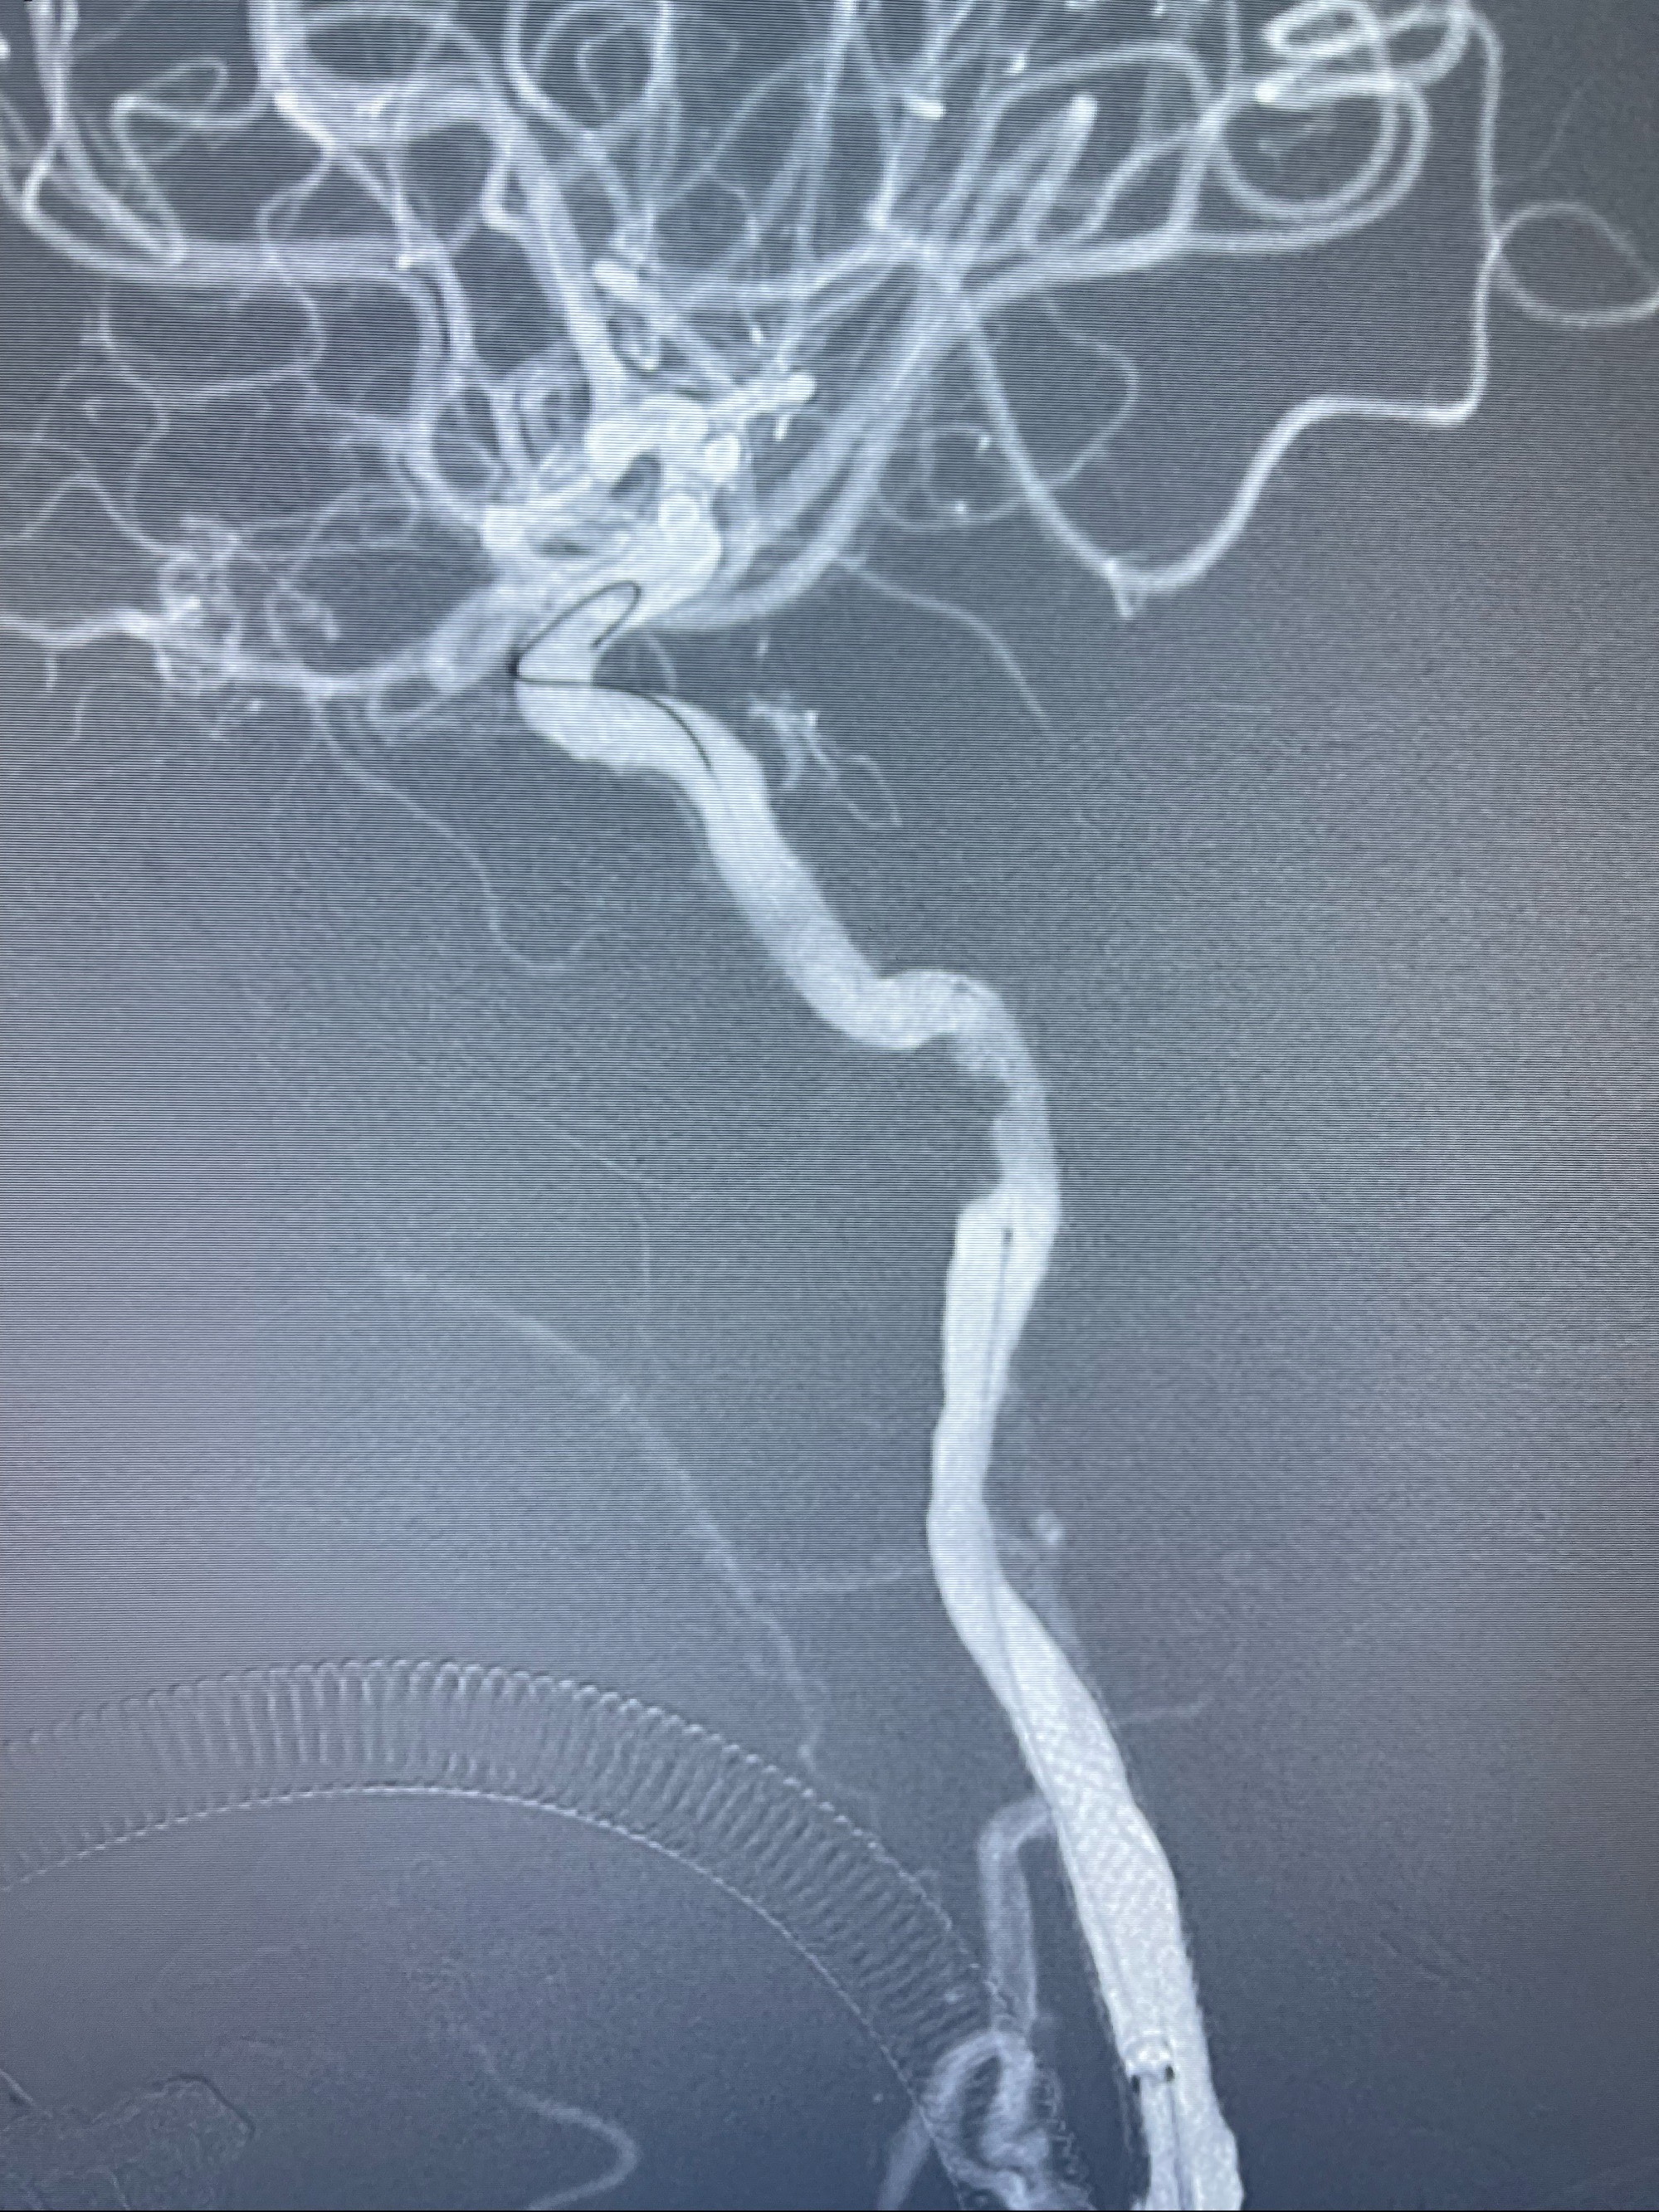

经导引导管造影显示支架远端颈内动脉不规则狭窄伴局部充盈缺损,同时行全身肝素化5ml

泄除球囊造影显示局部管腔扩张佳

即刻造影显示狭窄扩张佳

即刻造影显示支架贴壁佳

支架完全打开,近心端位于原颈动脉支架远心端内

麻醉苏醒佳,遵嘱活动!